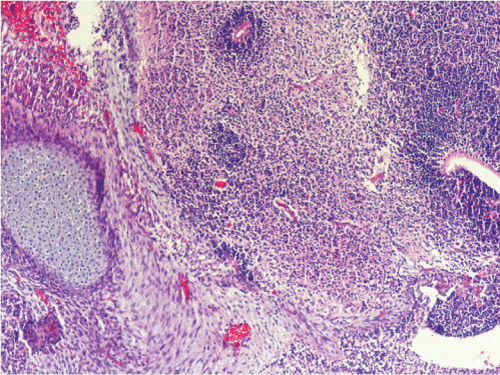

The mass was composed of mature components of all the three germ cell layers comprising stratified squamous epithelium, nervous tissue, intestinal epithelium, respiratory epithelium, adipose tissue, bone and cartilage tissue. Wide areas of immature neuroepithelial components comprising small round cells forming rosettes and tubules were also found. Therefore, pathologic final diagnosis was immature teratoma (grade 3) (Figure 4 and Figure 5).

Figure 5: Wide areas of immature neuroepithelial components comprising small round cells forming rosettes and tubules.